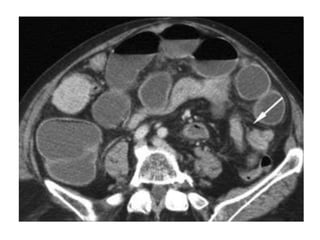

TC

• Cuando no llegamos al diagnóstico mediante

exploraciones menos costosas y más accesibles

• Muy útil en estudio de procesos

biliopancreáticos o abscesos y tumores

intestinales

• Demuestra aire en la pared intestinal, en el

interior de la vena mesentérica y la porta